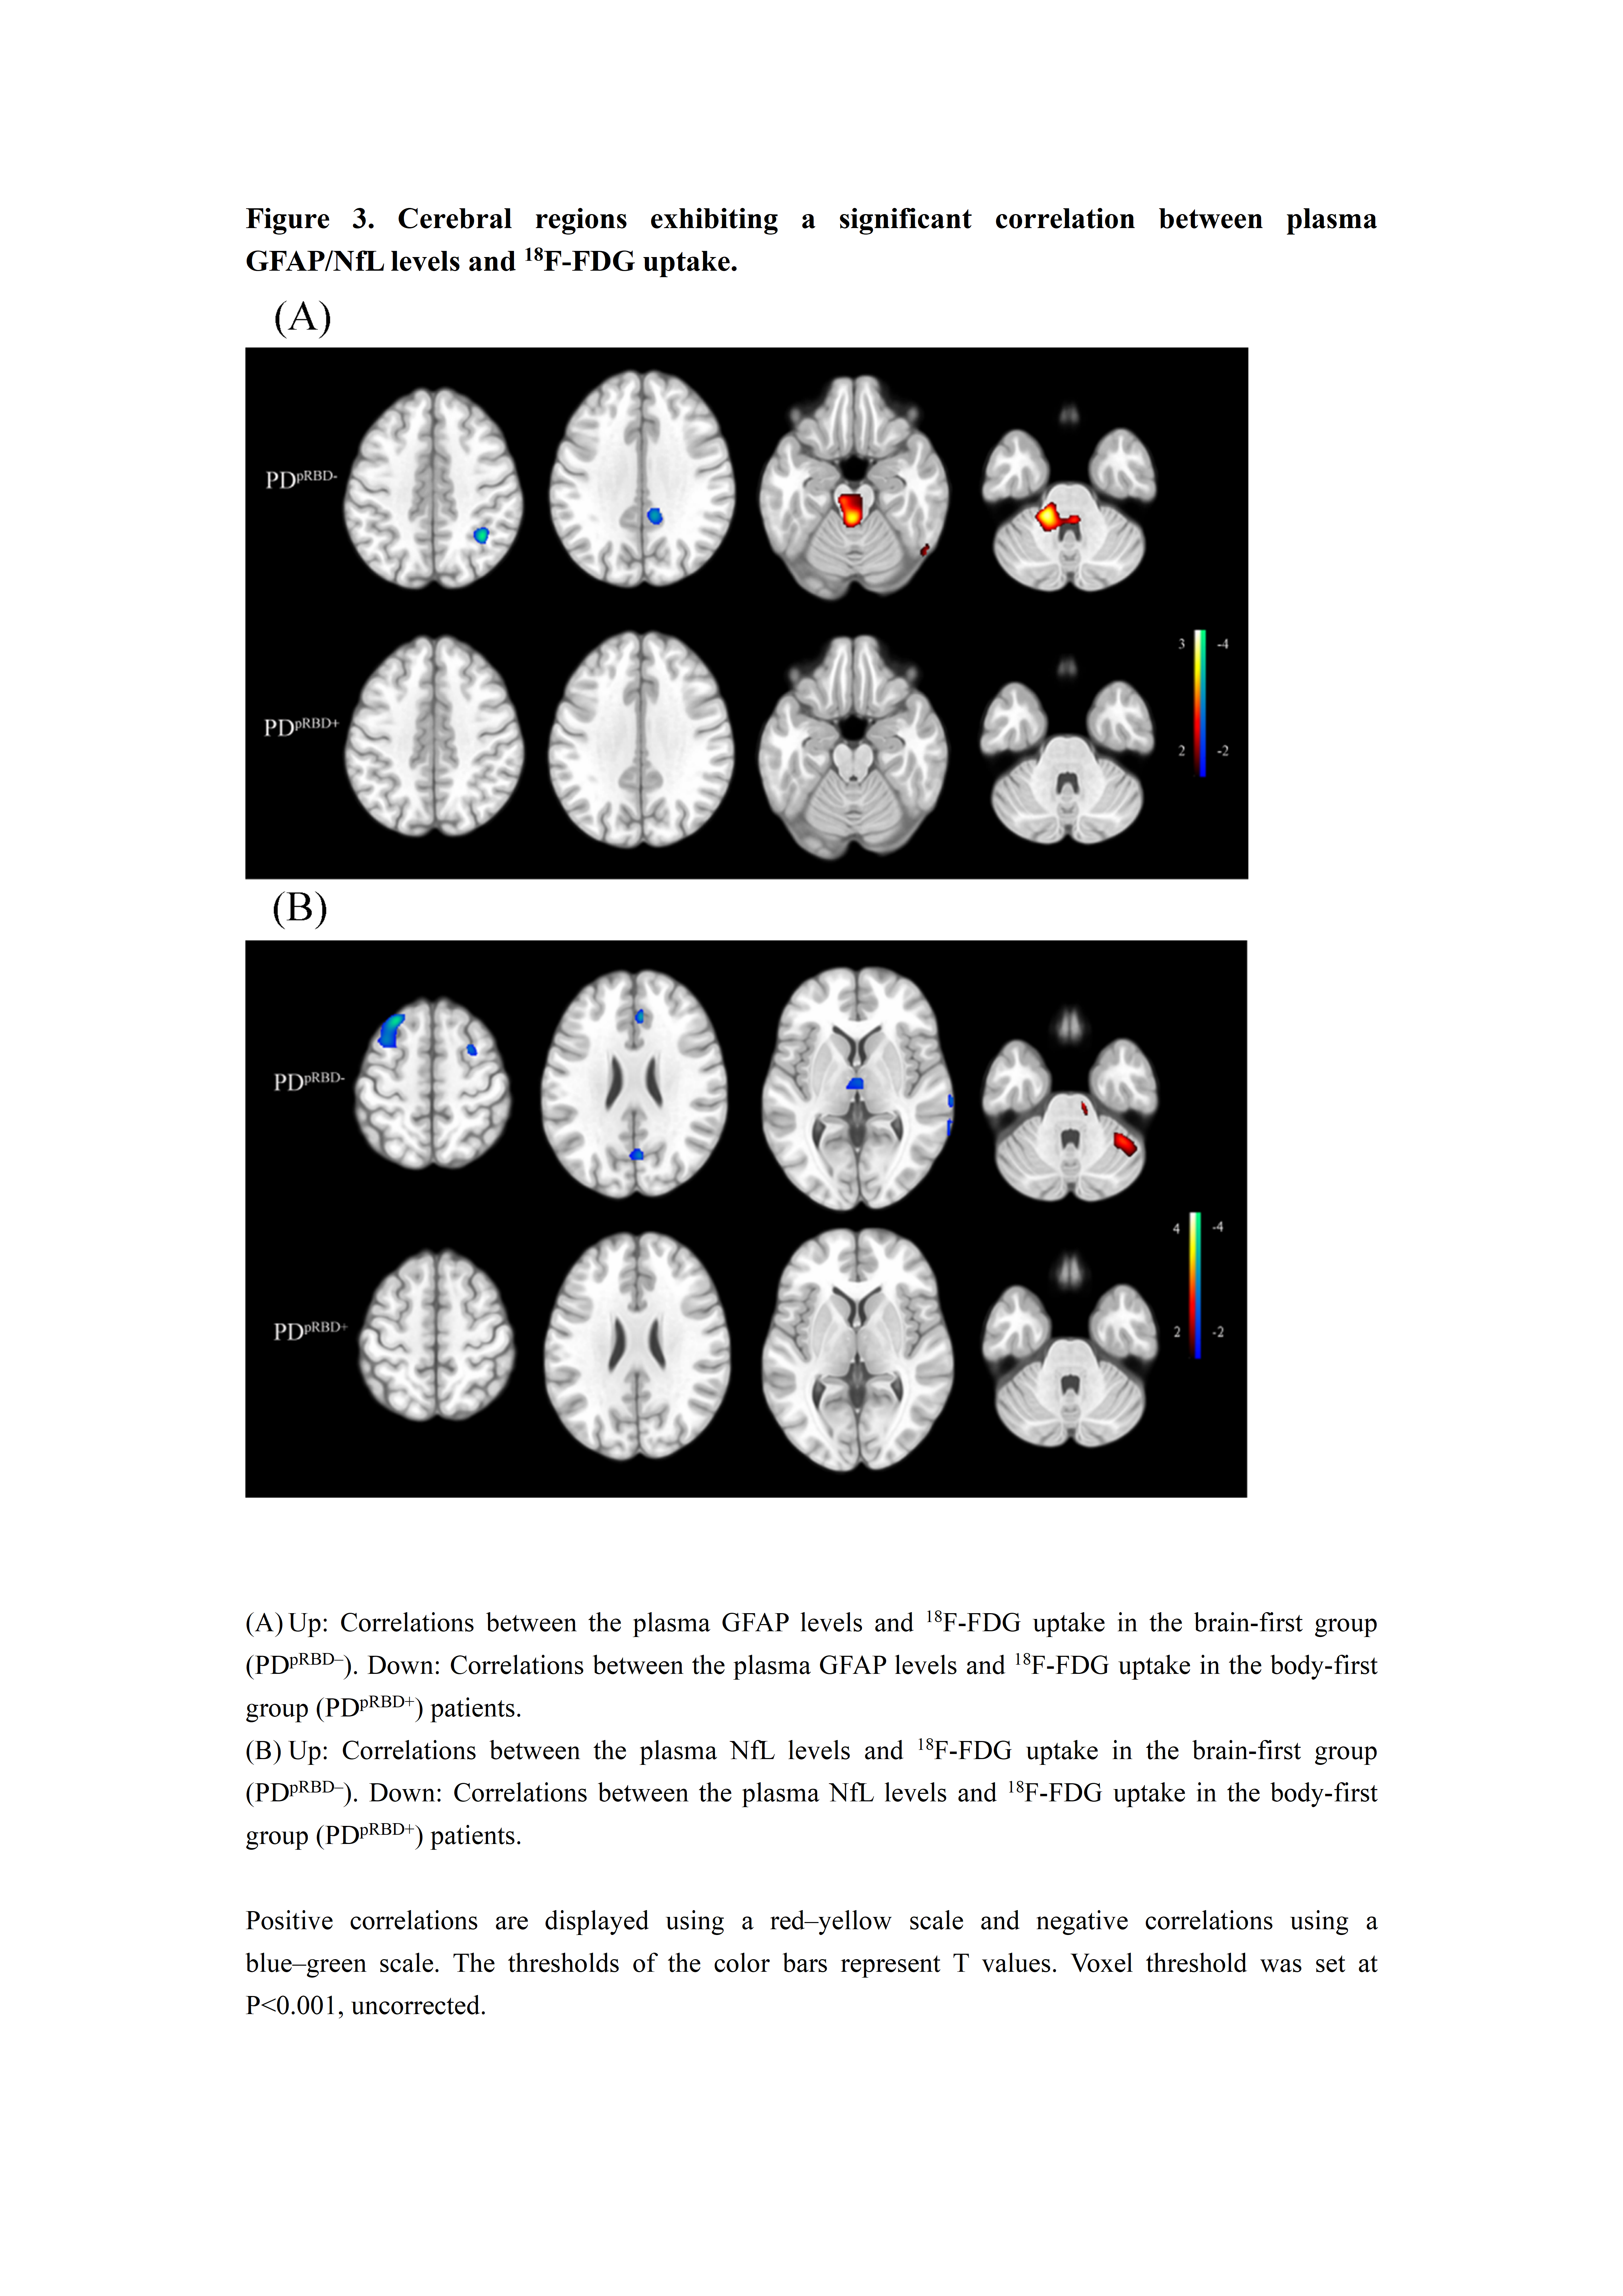

Results: The body-first group patients showed worse autonomic dysfunction (P=0.023) and lower quality of life (P=0.028) at baseline. Longitudinally, they showed faster motor progression (P=0.013) and greater decline in attention and working memory (P=0.003). Plasma GFAP (P<0.001) and NfL (P=0.042) were higher in the body-first group. Body-first patients showed reduced glucose metabolism in left middle temporal, bilateral middle occipital, and left inferior parietal gyrus (P<0.001). In the brain-first group, plasma GFAP was positively correlated with substantia nigra metabolism (r=0.38, P=0.003) and negatively with parietal cortex metabolism (r=-0.42, P<0.001). Plasma NfL was positively correlated with cerebellar metabolism (r=0.35, P=0.008) and negatively with anterior cingulate cortex metabolism (r=-0.41, P=0.001). No significant correlations were observed in the body-first group.

Figure 3